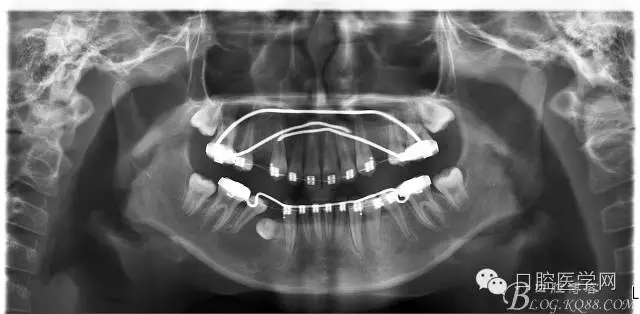

術(shù)后一個月 三個月 五個月 八個月 拔除第一雙尖牙后 曲斷片:

2:拔牙矯治,拔出4顆第一前磨牙。

3:上下頜利用拔牙間隙解除擁擠并內(nèi)收上下前牙,改善唇側(cè)貌。

5:上頜TPA+NanceArch強(qiáng)支抗.

6:下頜囊腫開窗引流,雙側(cè)第一恒磨牙舌桿保持牙位。擇期拔除第一前磨牙。